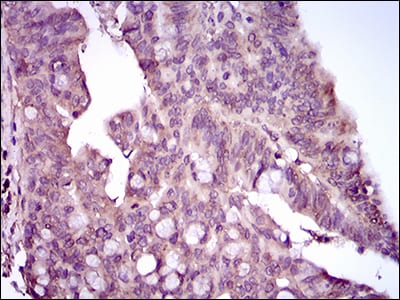

Immunohistochemical analysis of paraffin-embedded human rectum cancer tissues using MAPK14 mouse mAb with DAB staining.